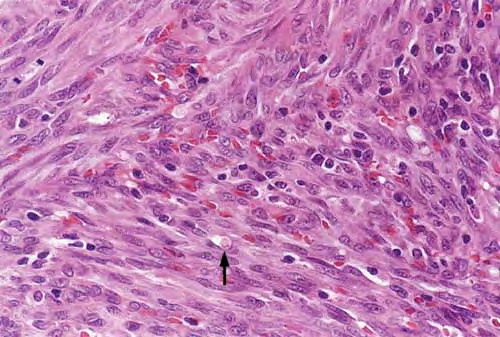

Nodular lesions consist predominantly of spindle cells arranged in bundles and interlacing fascicles and interspersed, irregular, slit-like vascular spaces without endothelial linings. Advanced lesions may display pronounced pleomorphism, nuclear atypia, and mitotic figures. At the periphery of solid tumors, (lymph) angiomatous-like portions of KS with bizarre vascular lumina and intravascular and extravasated erythrocytes, as well as siderophages, may be preserved. Erythrocytes, which appear as eosinophilic globules, are trapped within the slits and clefts formed by the spindle cells and erythrophagocytosis are occasionally observed. As in all other stages of KS, a moderate inflammatory infiltrate consisting of lymphocytes, histiocytes, plasma cells, and, sporadically, neutrophils is regularly present.